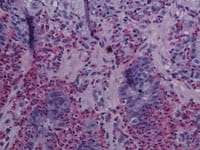

Eosinophilic Gastrointestinal Disorders

The CCED was the first center dedicated to eosinophilic disorders and now serves as a global leader and role model for understanding, elucidating, and treating eosinophilic gastrointestinal disorders (EGIDs). The CCED researchers under Dr. Rothenberg’s direction conduct leading basic, translational, and clinical studies to determine the causes of eosinophilic disorders, develop better treatments, and find a cure. The CCED has substantially contributed to the understanding of the clinical, epidemiologic, genetic, and pathogenetic etiology of EGIDs. Investigator-initiated studies have fueled the development of novel therapeutics and served as the primary site for multi-center drug trials.